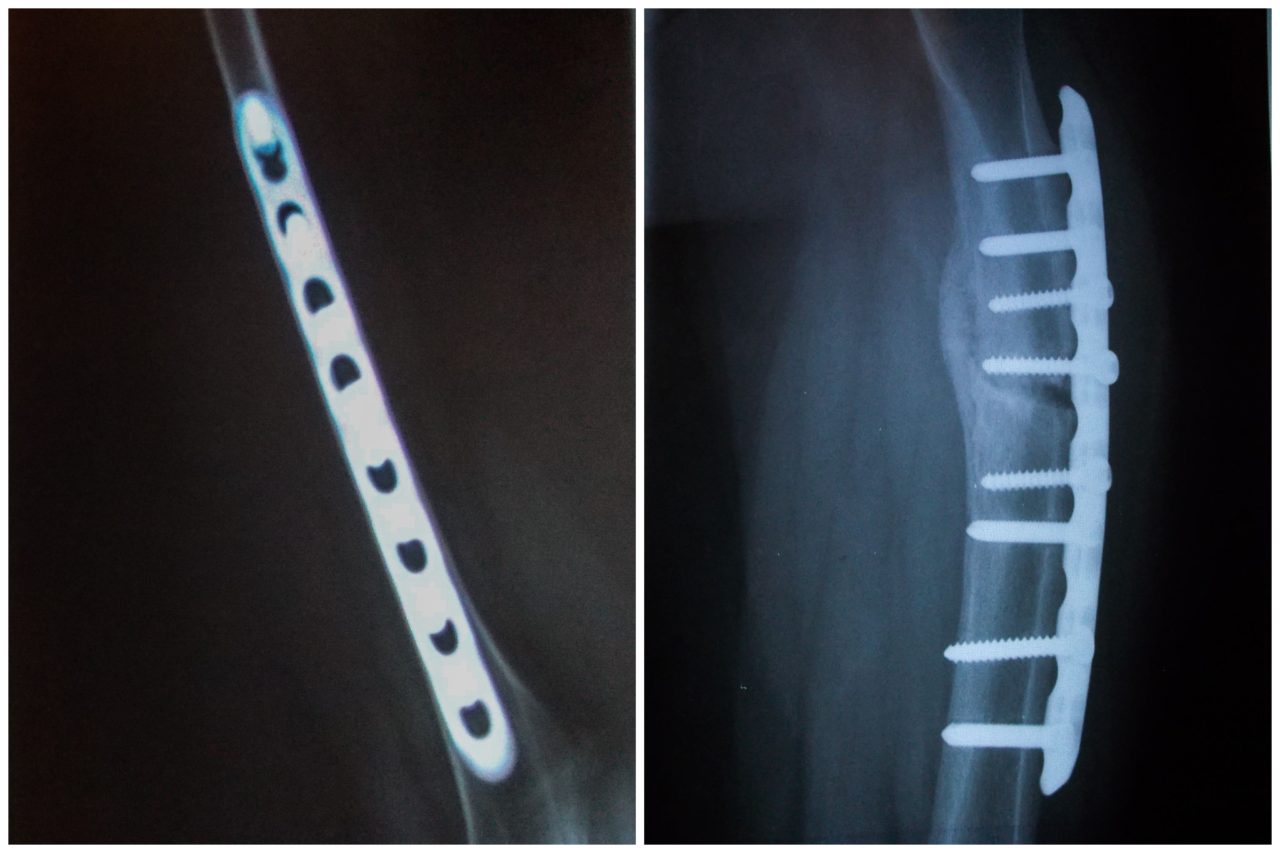

Рентгены Ваниных костей. Из домашнего архиваФото: Евгения Жуланова/SCHSCHI для ТД

Несовершенный остеогенез встречается у 6-7 человек из 100 тысяч — это общемировая статистика. В России его уже научились лечить, но Ване не повезло сразу попасть к специалисту, который бы правильно диагностировал это заболевание. Врачи после переломов ставили ему титановые пластины, которые крепятся болтами прямо к костям, а кости у мальчика слишком хрупкие. Эти пластины для остеогенезников — катастрофа.

В мире уже существует более технологичное изобретение — штифты. Это стержни, которые ставятся внутри кости, чтобы повысить ее прочность. Но до сентября этого года в России телескопические штифты, которые растут вместе с костью, не были зарегистрированы. Удалось это лишь благодаря многолетним усилиям фонда «Хрупкие люди». Теперь операции со штифтами могут проводить в российских клиниках, и это дает надежду всем «хрупким», кого в будущем ждала только инвалидная коляска.